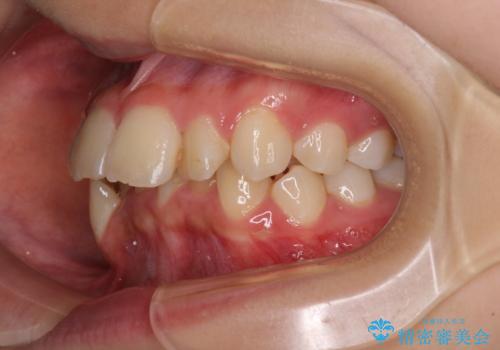

- 前方に飛び出した前歯と、下顎の八重歯を気にして来院された患者様です。

口元の突出感を改善するため、上下左右の第一小臼歯4本を抜歯し、ワイヤー装置にて矯正治療を行うこととしました。

抜歯矯正により、口元の印象だけでなく、横顔の印象も大きく改善されました。